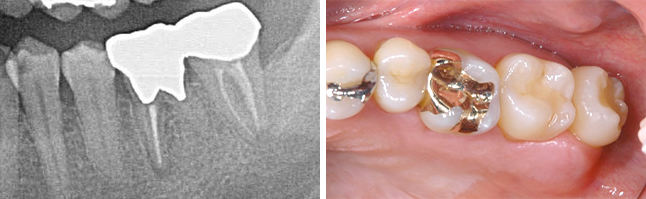

過去に抜歯と言われ インプラントを薦められた38歳女性の患者

BEFORE

向かって左から3番目の大きな歯が割れており、抜歯を余儀なくされました。

レントゲンです。 割れた歯の周囲の骨が感染により溶けて黒くなっています。向かって最右が移植する親知らずです。

AFTER

感染が大きかったことから割れた歯を抜歯後4週を待って同測の親知らずを移植し、約2ヵ月後にセラミック製のクラウンを被せました。 根の治療が済み、レントゲンは術後3年のものですが、異常なく安定しているのがわかります。